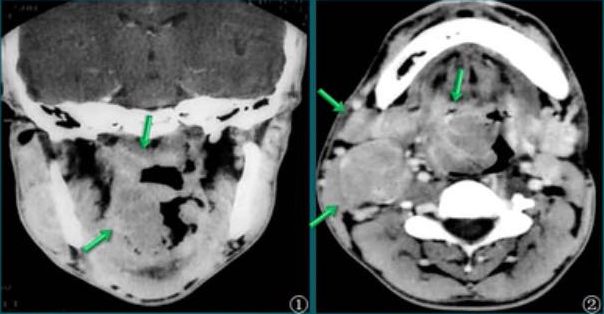

淋巴瘤

肿块侵犯鼻咽、口咽、边缘清楚,密度均匀,无明显强化;右侧淋巴结受侵。 医学百科网 | YxBaike.Com